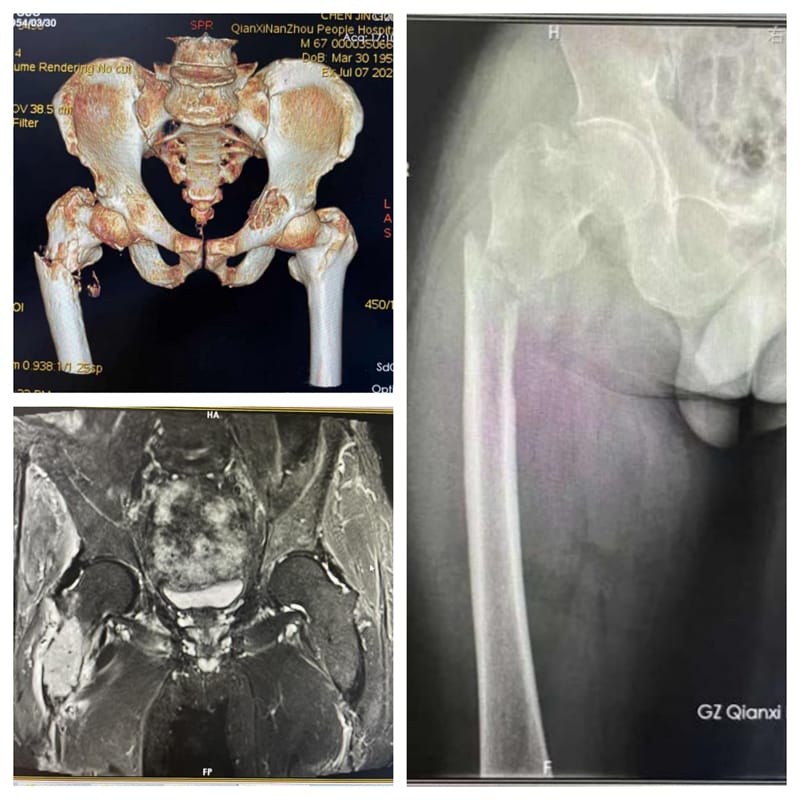

患者陈某,68岁,右下肢剧痛不能行走,经检查确诊为右股骨上段骨肉瘤病理性骨折。考虑到患者“髋关节下病变没有支撑”,关节外科为其施行了“股骨上段骨肉瘤切除,髋关节置换重建”手术。术后经过医疗团队的精心治疗及护理,患者恢复较好,很快便能下床行走。

术前右股骨恶性肿瘤浸润、股骨骨折